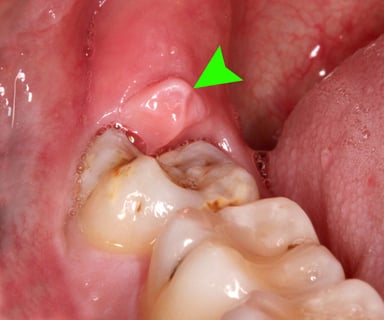

Viêm lợi trùm sẽ gây ra sưng đau và khó chịu cho người bệnh

Viêm lợi trùm vị trí răng cửa là một tình trạng phổ biến trong lĩnh vực nha khoa. Tình trạng này xảy ra khi các mảng vi khuẩn và mảng bám tích tụ, gây viêm ở dưới nướu. Khi vi khuẩn này phát triển, cơ thể phản ứng bằng cách gửi các tế bào miễn dịch đến vùng viêm. Điều này gây ra đau và sưng tại nơi nướu tiếp xúc với răng.

Khi viêm lợi trùm xảy ra có thể dẫn đến đỏ, sưng và chảy máu nướu khi chải đánh răng… Nếu không được điều trị, vi khuẩn có thể lan rộng, tổn thương đến các mô xung quanh răng. Từ đó, tình trạng sẽ dẫn tới viêm nướu sâu hơn và ảnh hưởng đến mô liên kết răng và xương hàm.